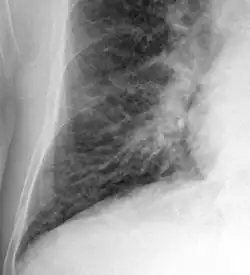

Kerley B lines in radiograph of acute cardiac decompensation. The short, horizontal lines can be found everywhere in the right lung.

Chronic stable heart failure may easily decompensate (fail to meet the body's metabolic needs). This most commonly results from a concurrent illness (such as myocardial infarction (a heart attack) or pneumonia), abnormal heart rhythms, uncontrolled hypertension, or a person's failure to maintain a fluid restriction, diet, or medication.[50]